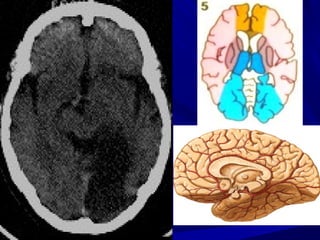

GIAI ÑOAÏN CAÁP SÔÙM (6-24 GIÔØ)

-Giaûm ñaäm ñoä ôû haïch neàn

-Maát ranh giôùi chaát traéng – xaùm

-Daáu daûi baêng thuyø ñaûo (insular ribbon

sign)

-Xoaù raõnh naõo

-Khoâng thaáy baát thöôøng

Mờ Khe Sylvius

Khe Sylvius

Không thấy

Mờ rãnh vỏ não và giảm đậm độ